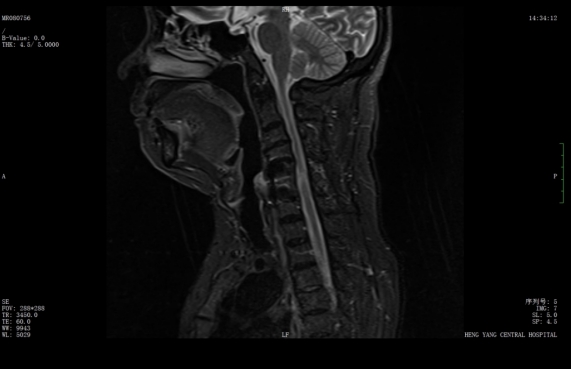

wps1.jpg

術(shù)前核磁共振提示:頸椎椎管狹窄、頸脊髓信號(hào)改變